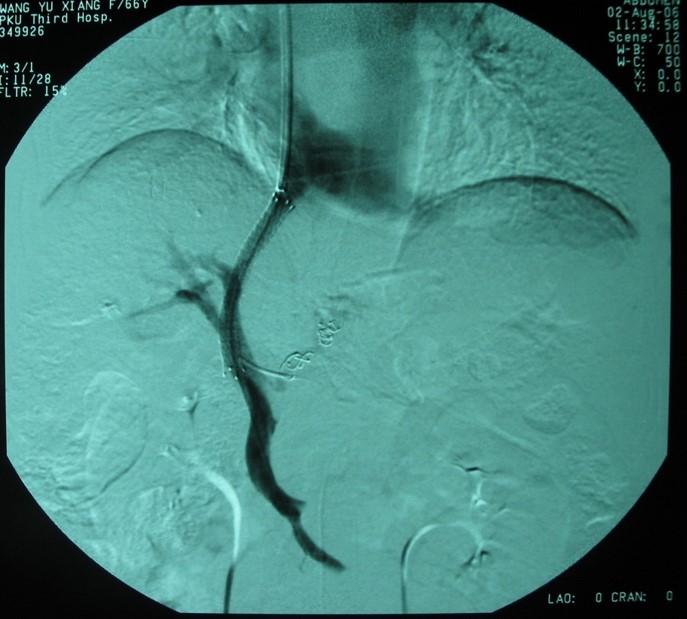

肝靜脈壓力梯度測(cè)定(HVPG)

對(duì)門靜脈高壓進(jìn)行精確量化評(píng)估和危險(xiǎn)度分層,指導(dǎo)不同危險(xiǎn)分層治療策略,本技術(shù)省內(nèi)領(lǐng)先。

肝靜脈壓力梯度測(cè)定